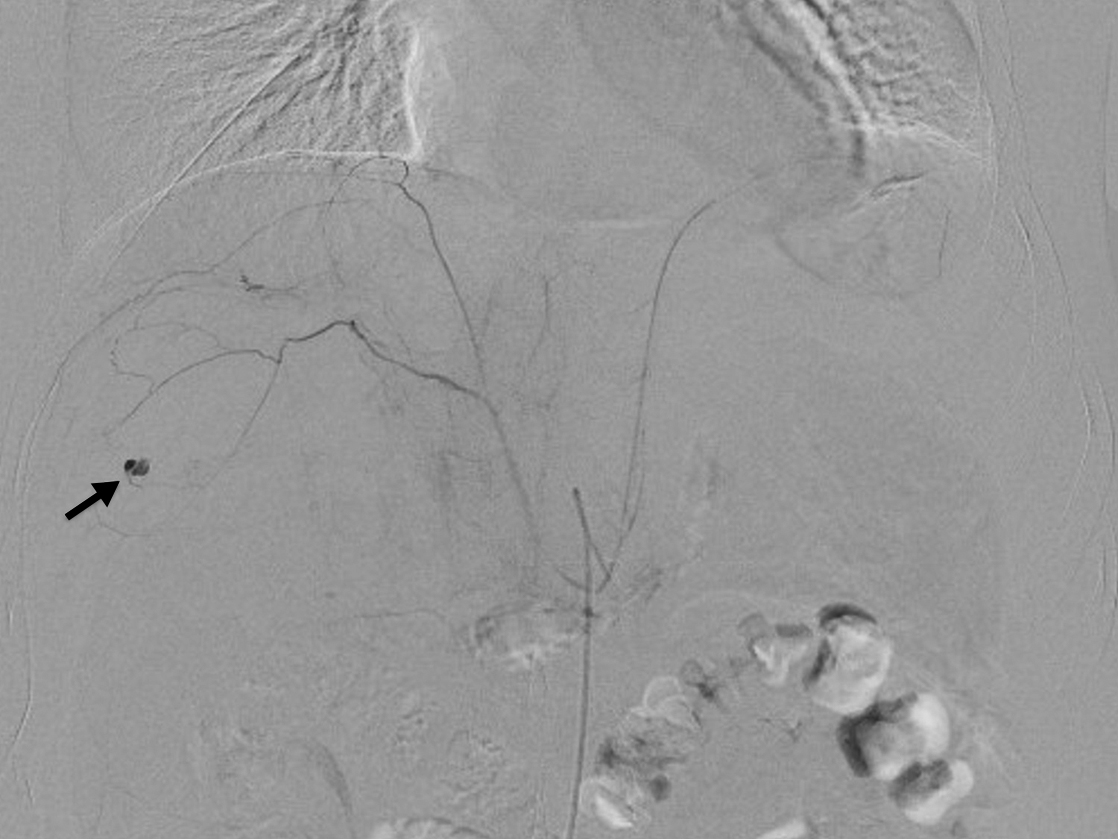

血管造影検査所見:右下横隔動脈からの出血を認め,塞栓術を施行した(Fig. 5).左下横隔動脈からの出血は認めなかったが,血管の攣縮による一時的な止血であり,再出血の可能性が高いと判断し,翌日に左も塞栓術を施行した.

Angiography shows extravasation of the contrast agent from the right inferior phrenic artery (arrow).